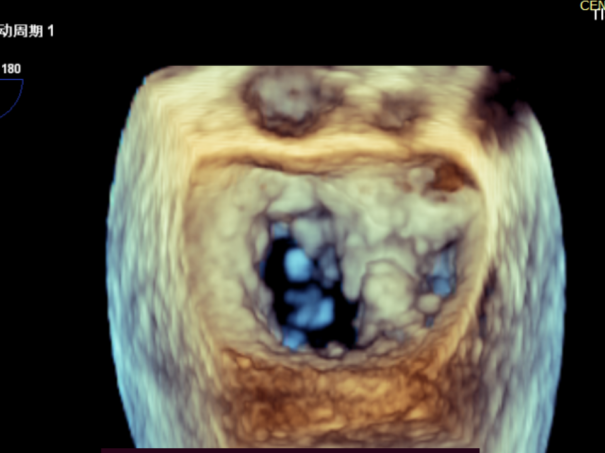

患者全麻后在超声和射线引导下穿刺股静脉-房间隔,器械顺利到达病变的二尖瓣区域,成功完成二尖瓣夹合后,患者二尖瓣反流即刻显著下降,左房压力即刻减低,预示着患者的临床症状将会得到明显改善。